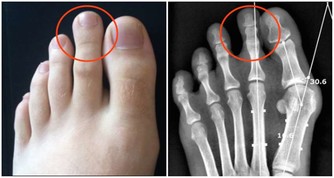

無名指疼痛:無名指和食指長度相同的人突發心臟病的幾率較高。